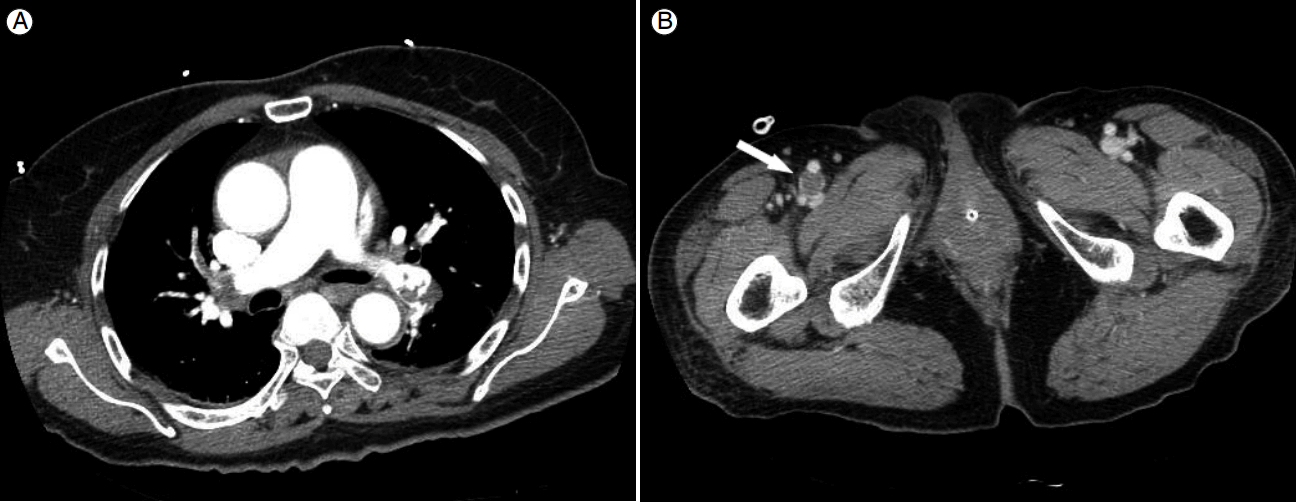

Figure 3.

Computed tomography images. (A) Thrombosis in both pulmonary arteries. (B) Thrombosis (arrow) in the right superficial femoral vein.